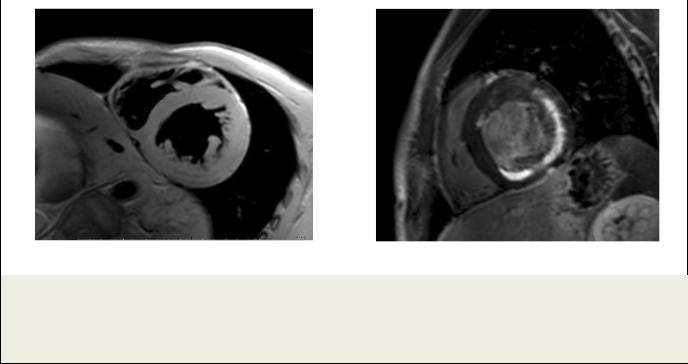

Рис. 4. МРТ сердца с отсроченным контрастированием.

Пациент Н., острый миокардит; а – Четырехкамерная длинная ось ЛЖ; б – двухкамерная длинная ось ЛЖ. Видны множественные мелкие очаги накопления КС во всех стенках ЛЖ.